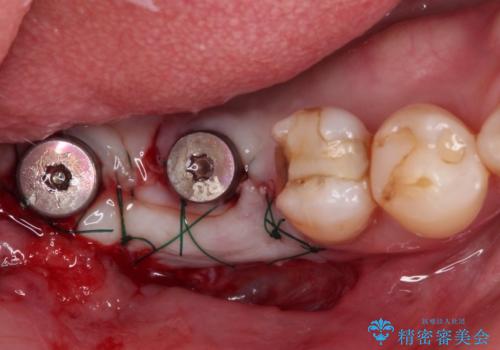

診察したところ、前歯は反対咬合であり、その影響で抜歯が必要な奥歯があることが分かりました。

抜歯が必要な奥歯は、インプラント並びにブリッジにより補綴を行い、上下前歯は反対咬合を改善させるように補綴治療を行うこととしました。

健全な歯を削ってセラミッククラウンに置き換えることは、本来避けるべき治療と考えますが、今回は①患者様が60歳を越えていること、②要改善の咬合により抜歯が必要な奥歯があること、③反対咬合の前歯改善の手段としてセラミック治療が選択肢にあることなどから、全顎的なセラミック治療を行うこととしました。